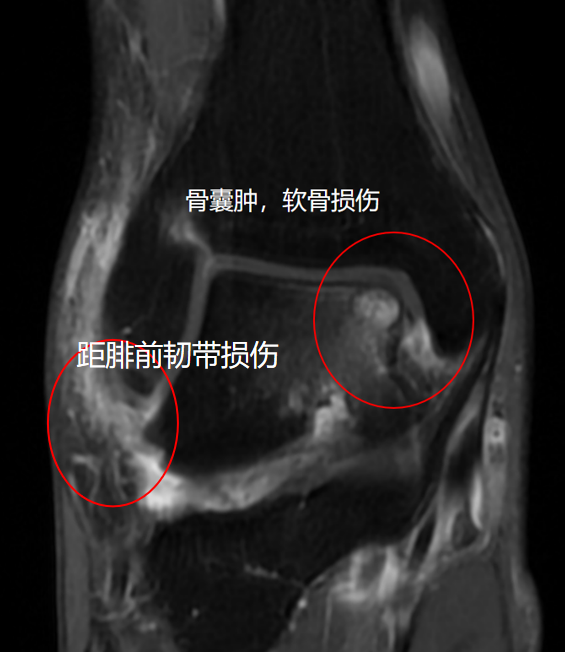

经查体,该患者右踝关节前抽屉试验阳性,内翻应力实验阳性,前外侧关节间隙压痛。踝关节距腓前韧带失效,踝关节不稳明显。完善踝关节DR及MRI检查。

根据病情决定行关节镜下右踝关节腔探查清理+外侧副韧带修复+距骨病灶清除+自体骨软骨移植术。

踝关节不稳是指踝关节周围韧带受损后导致踝关节不稳定,而引起踝关节频繁扭伤的现象,是踝关节扭伤后较容易遗留的问题,患者经常形成扭伤—不稳—再次扭伤的恶性循环。因不稳定造成的踝关节反复扭伤可造成关节软骨的损伤,重者可形成创伤性关节炎,从而严重影响患者的生活质量。 由于软骨再生能力较差,对于面积大、深度深、伴有囊肿形成的严重软骨损伤,软骨移植是目前公认的最佳治疗手段,膝关节非负重区软骨是移植的一个理想供区。